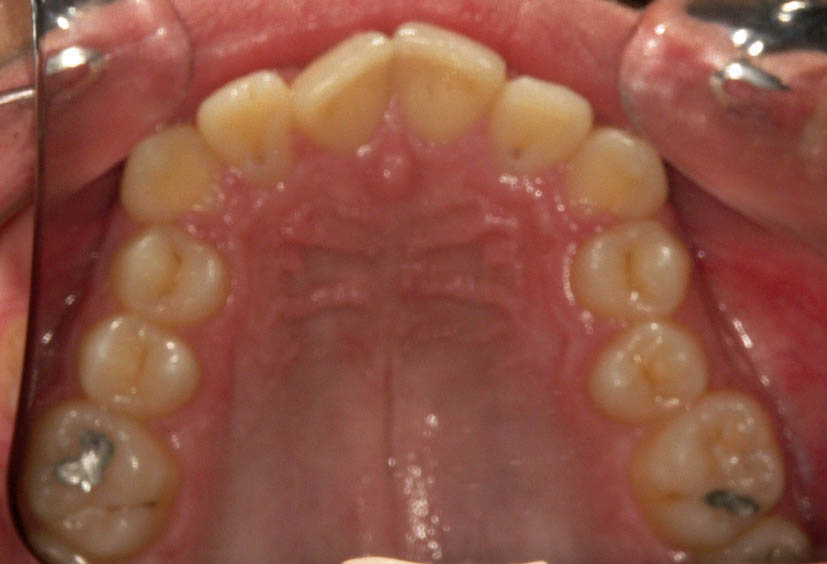

شکل 101-2: نمای اکلوزال بالا